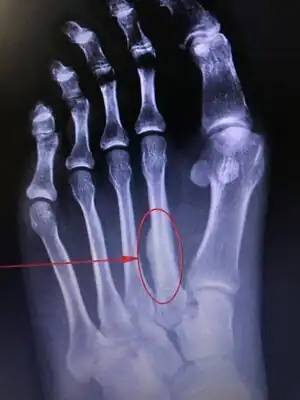

March fracture, is the fracture of the distal third of one of the metatarsals occurring because of recurrent stress. It is more common in soldiers, but also occurs in hikers, organists, and people whose duties entail much standing (such as hospital doctors). March fractures most commonly occur in the second and third metatarsal bones of the foot.[1][2][3] It is a common cause of foot pain, especially when people suddenly increase their activities.[4]

The onset is not dramatic. When the boot or shoes are taken off, there is a cramp-like pain in the affected forefoot, and moderate local edema appears on the dorsal aspect. On moving each toe in turn, that of the involved metatarsal causes pain, and when the bone is palpated from the dorsal surface, a point of tenderness is found directly over the lesion. Radiography at this stage is negative, but the condition is diagnosed correctly by military surgeons without the aid of x-rays. In civil life, it is seldom diagnosed correctly for a week or two, when, because of lack of immobilization, there is an excessive deposit of callus (which may be palpable) around the fracture.[1]

X-ray is seldom helpful, but a CT scan and an MRI study may help in diagnosis.[5] Bone scans are positive early on. Dual energy X-ray absorptiometry is also helpful to rule out comorbid osteoporosis.[6]